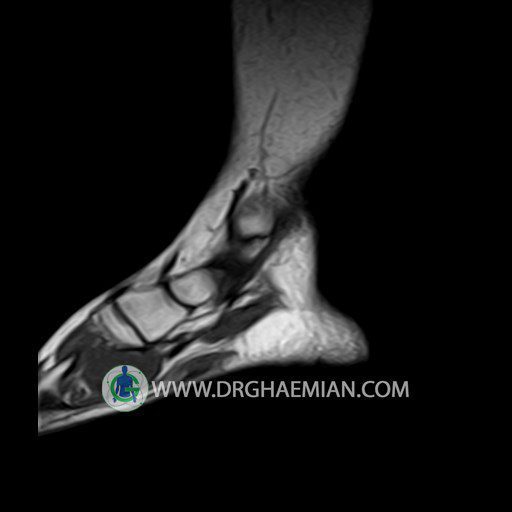

پزشکان اغلب از تصویربرداری ام آر آی برای تشخیص و درمان عارضه های پزشکی که فقط با استفاده از اشعه ایکس یا میدان مغناطیسی و امواج رادیویی قابل مشاهده است، استفاده می کنند. دستگاه ام آر آی تصاویر دقیق از ساختار های داخلی بدن ایجاد می کند. در این کیس تورم مچ پا بیمار مشاهده می شود.

Technique: Sagittal T1, T2 , Axial GE , coronal & sagital fatsat .